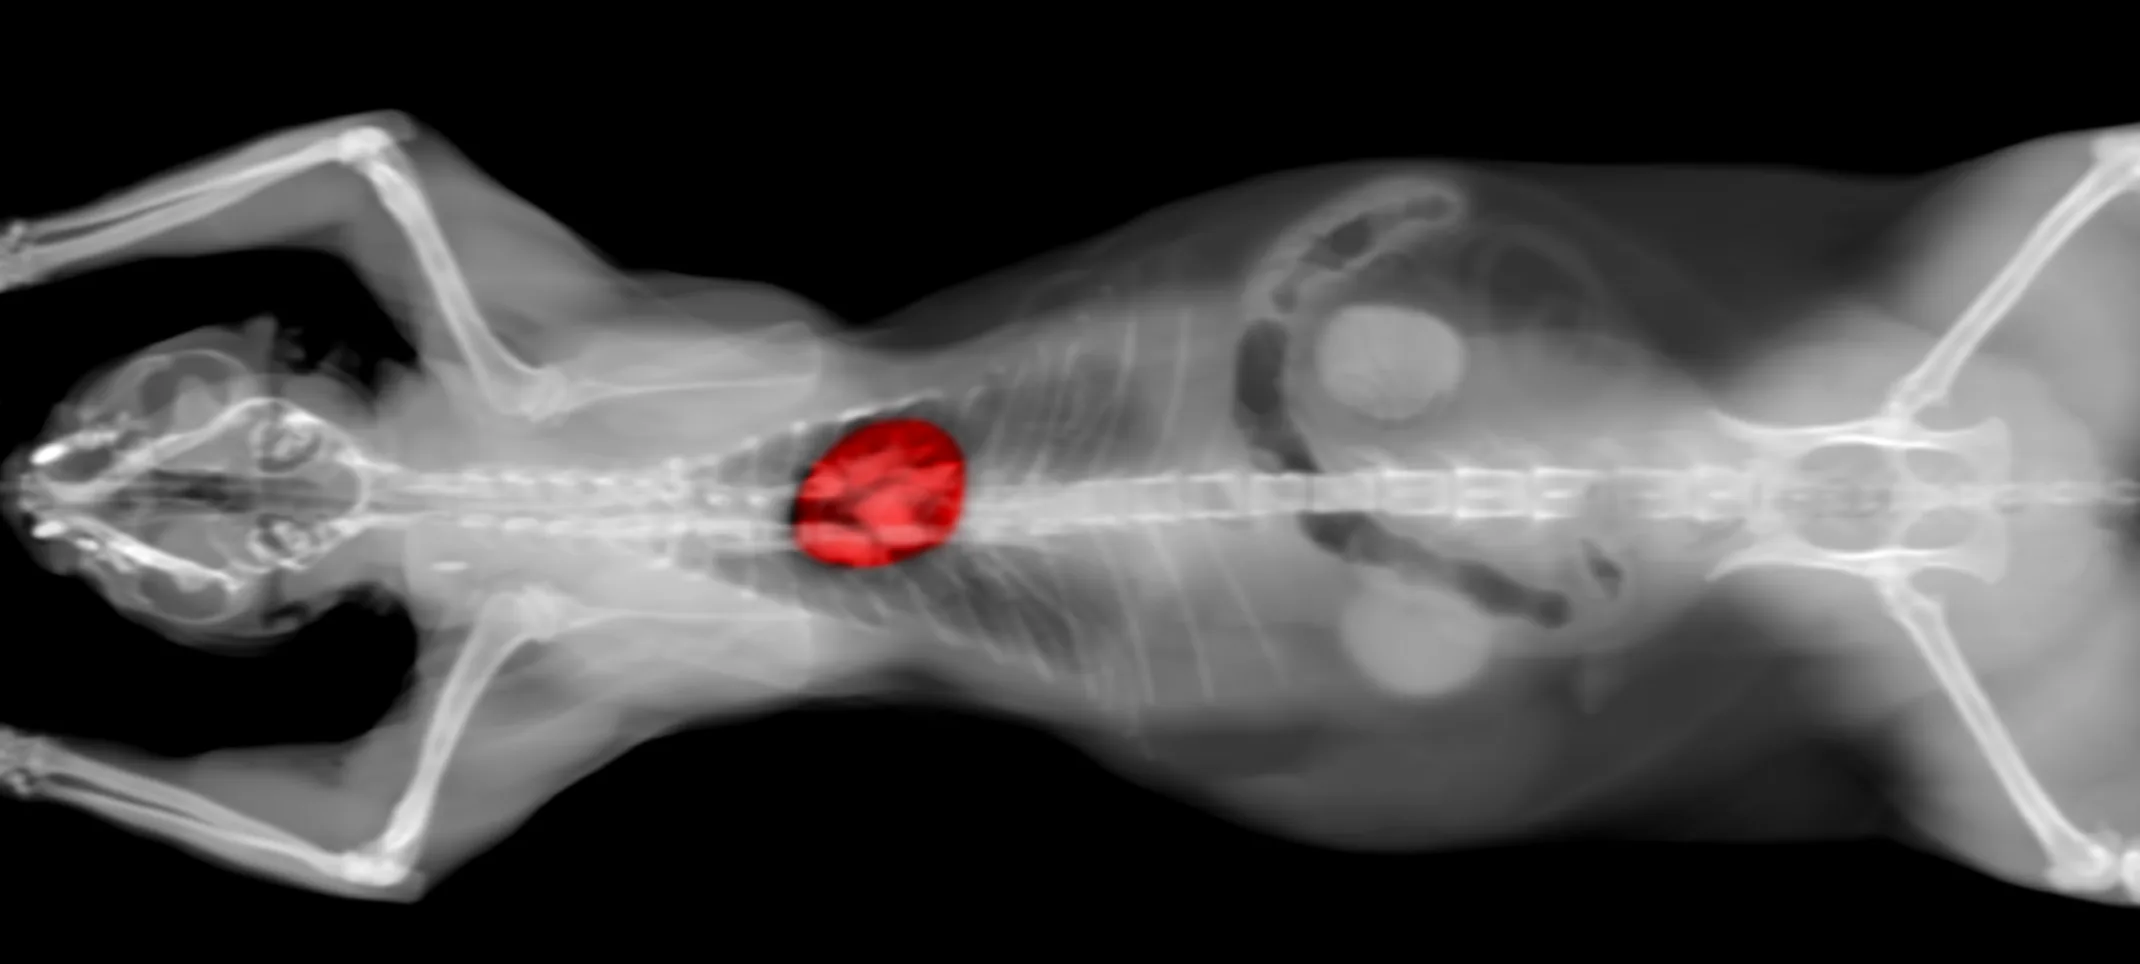

Computed Tomography is a way of examining bodily organs by scanning them with X rays and using a computer to construct a series of cross-sectional images that run along a single plane.

During the test, the patient lays on a table that is attached to the CT scanner. The CT scanner is a very large doughnut-shaped machine with a hole large enough for the table the patient is laying on to pass through. The CT scanner sends X-rays through the area of the body that is being studied. Each rotation of the scanner produces a thin photo slice of the area. All of the pictures are then put together in the computer to create a complete image.

A Computed Tomography Scan can be used on nearly any part of the body including the heart, lungs, chest, belly, pelvis, arms and legs. It can take pictures of bodily organs, such as the liver, pancreas, intestines, kidneys, bladder and glands. It also can study cardiovascular systems, bones, and the spinal cord.